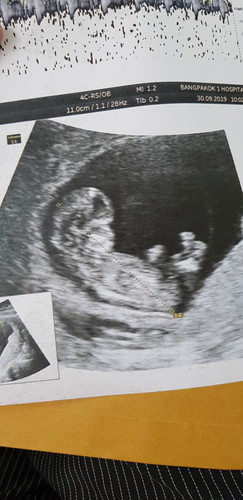

11w 1d อาทิตย์หน้าตรวจนิฟตี้แล้ว ขอให้หนูปลอดภัยนะลูก

เราอายุ 38 แล้ว ความเสี่ยงสูง กลัวโครโมโซมผิดปกติจังค่ะ ไม่อยากแท้งอีกแล้ว TT (ท้องสองค่ะ ท้องแรกโดนขูดมดลูกไปเพราะตัวอ่อนไม่มีหัวใจ)